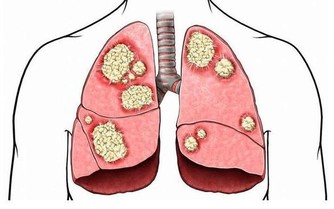

注意!被壁虱咬到,千萬不要直接拔出來!只要這樣一吸...接下來的畫面你絕對不敢想像!